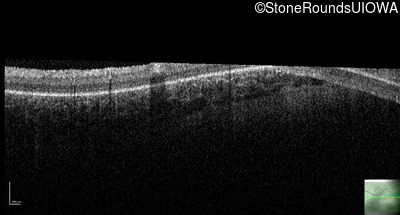

Optical Coherence Tomography - Right - No Light Perception

Exemplar / OCT Stack